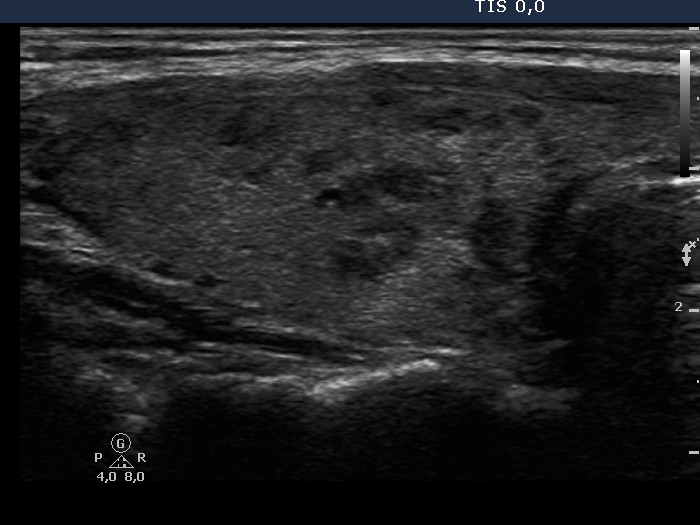

Follow-up investigation 32 months after first visit (ultrasonographic picture 2)

Patient 14 months after discontinuation of thyrostatic therapy in hyperthyroid state

Right lobe, longitudinal scan.